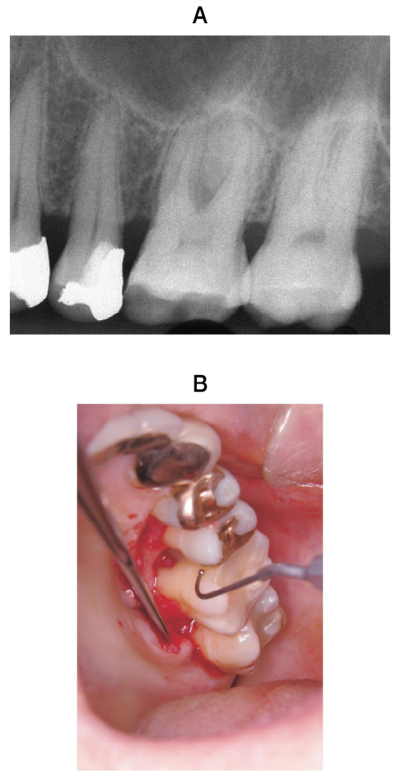

50歳の男性。上顎左側第一大臼歯部の違和感を主訴として来院した。1年前から自覚していたがそのままにしていたという。歯周基本治療後の再評価の結果、歯周外科治療を行うこととした。術前のエックス線画像と術中のスケーリング・ルートプレーニング<SRP>中の口腔内写真を別に示す。再評価時の歯周組織検査結果の一部を表に示す。

SRPに続いて行う処置として適切なのはどれか。1つ選べ。